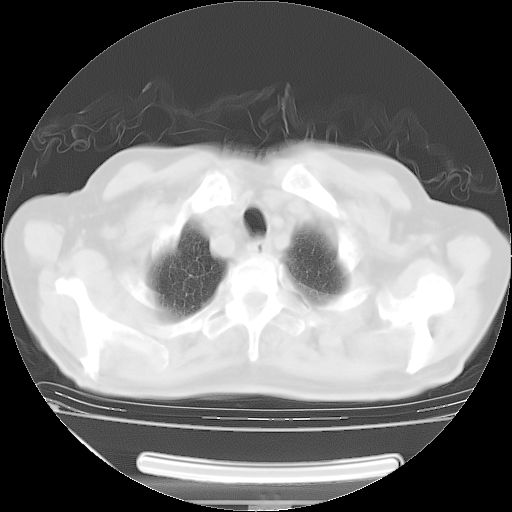

今天复查肺部CT,发现双肺广泛磨玻璃样改变。所以我把3月19日和5月9日相隔50天的肺部CT上传。请大家会诊。

5月9日肺部CT(在4月27日齐鲁医院肺部CT描述部分肺组织磨玻璃样改变,12天后肺组织广泛磨玻璃样改变)

2009年5月9日肺部CT

大致读了系列胸部CT:纵隔窗无明显异常,肺窗:从4、27至今:主要是双肺中下野外带可见毛玻璃样改变,目前处于急性肺泡炎阶段,至于原因考虑1、结替组织或胶原血管性疾病所致?2、恶性疾病如恶组在肺部所致的表现或细支气管肺泡癌?3、药物或其它原因如肺蛋白沉着症所致肺泡炎目前不太可能?总之,明天就去请我院的呼吸科、感染科、血液科和临免专家会诊哈。